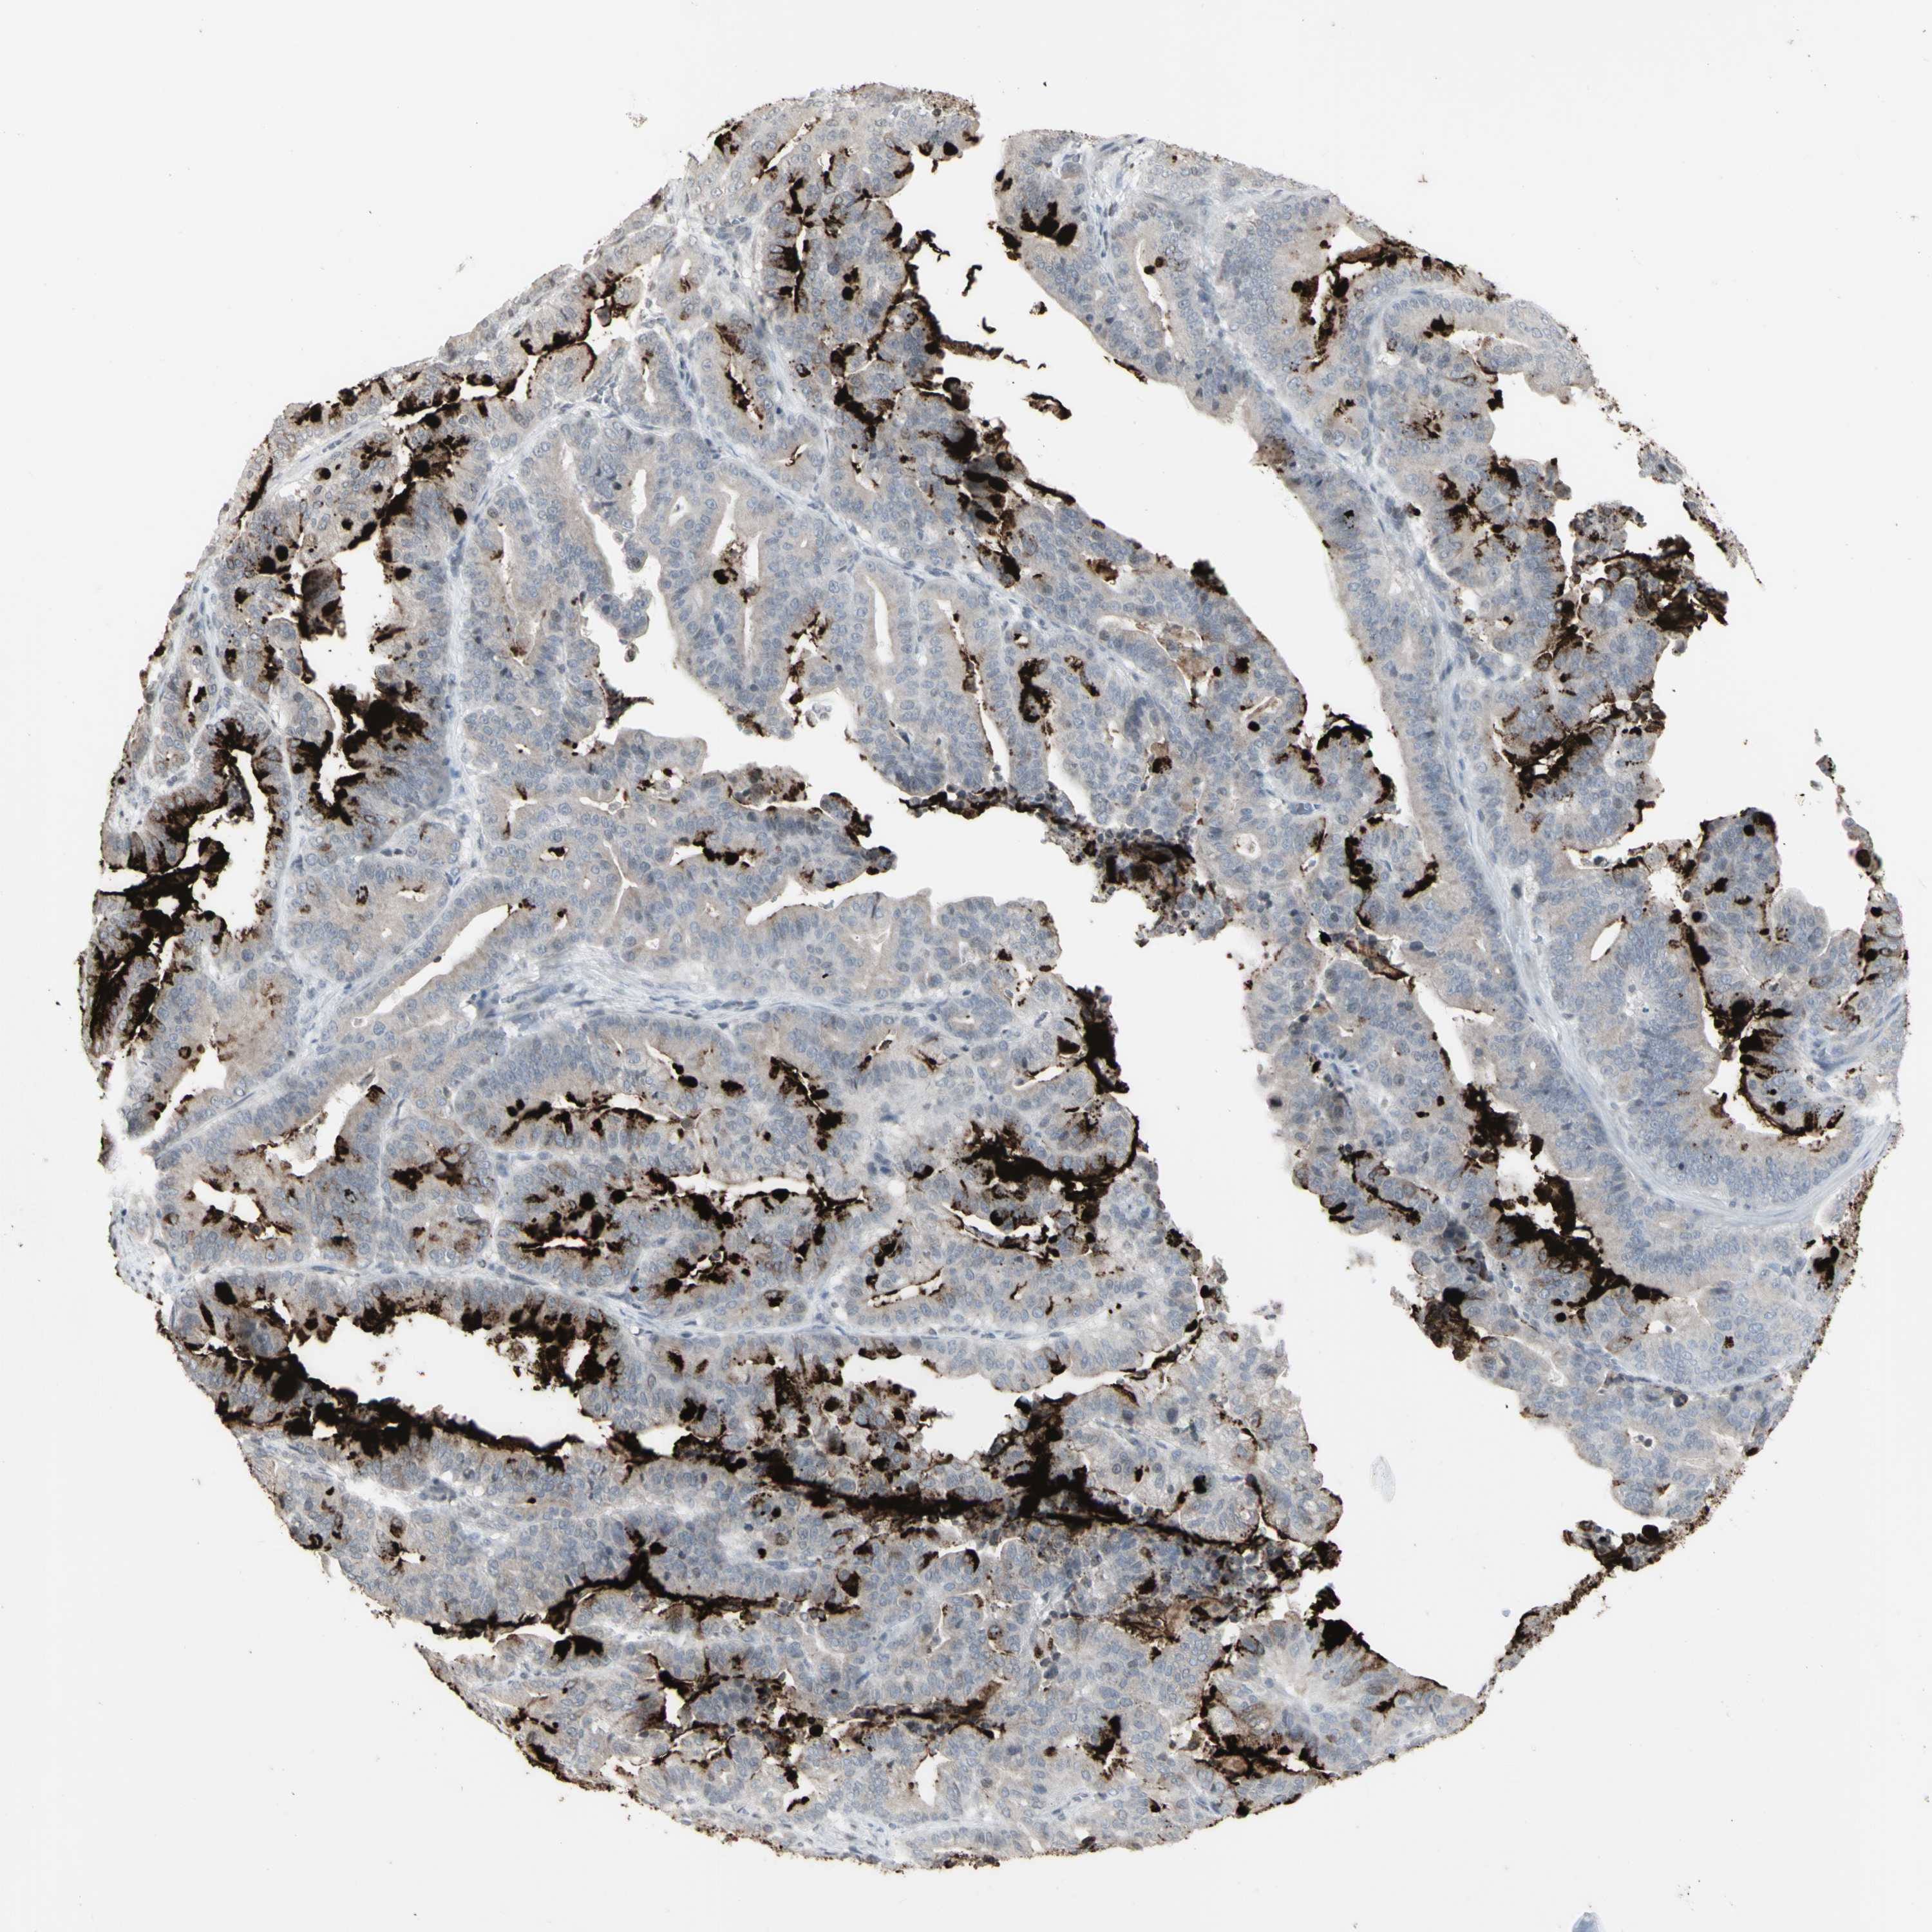

PANCREATIC CANCER - Protein expressioni

A mouse-over function shows sample information and annotation data. Click on an image to view it in a full screen mode. Samples can be filtered based on level of antibody staining by selecting one or several of the following categories: high, medium, low and not detected. The assay and annotation is described here.

Note that samples used for immunohistochemistry by the Human Protein Atlas do not correspond to samples in the TCGA dataset.

Antibody stainingi

Antibody staining in the annotated cell types in the current human tissue is reported as not detected, low, medium, or high, based on conventional immunohistochemistry profiling in selected tissues. This score is based on the combination of the staining intensity and fraction of stained cells.

Each image is clickable and will lead to virtual microscopy that enables deeper exploration of all samples and also displays staining intensity scores, fraction scores and subcellular localization as well as patient and tissue information for each sample.

HPA040615

HPA070378

HPA077637

CAB002774

CAB009395

Staining

High

Medium

Low

Not detected

Intensity

Strong

Moderate

Weak

Negative

Quantity

>75%

75%-25%

<25%

None

Location

Nuclear

Cytoplasmic/membranous

Cytoplasmic/membranous,nuclear

Adenocarcinoma, NOS

Adenocarcinoma, metastatic, NOS